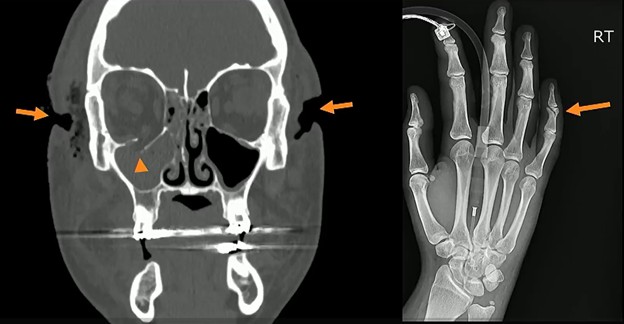

- Defensive Upper Extremity (UE) + Target Craniofacial Injuries

- Craniofacial: CT revealed multiple lacerations and facial fractures, including fracturing of the right orbital floor.

- Defensive: Radiography revealed a right-sided fifth middle phalangeal fracture, characteristic of defensive positioning.

Chronic Injuries: Injuries of different ages—such as the acute periorbital hematoma alongside a chronic nasal bone fracture below—are highly suspicious for repeated cycles of abuse.

- Recurrence: Chronic fractures of the extremities and nasal bones are significantly more frequent among victims of IPV, compared to matched controls.

- Consistency: Suspicion increases when old and new injuries involve the same target or defensive side, such as the midface, hands, feet, or ankles.